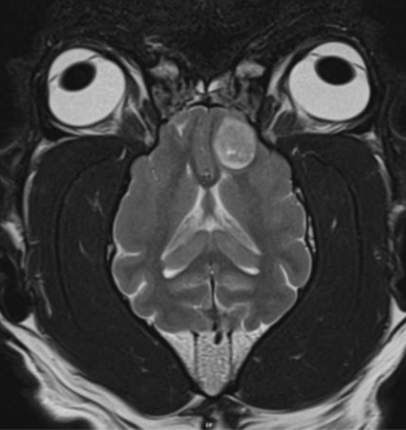

Figur 1. T2W dorsal MRI bild visar av en Fransk bulldog med en neoplastisk förändring, sannolikt ett gliom, i vänster frontallob.

Figur 2. Transversal DT bild av en ung chihuahua med grav hydrocefalus

Figur 3. T2W transversal MRI bild av en chihuahua med meningoencefalit av okänd etiologi (MUE)